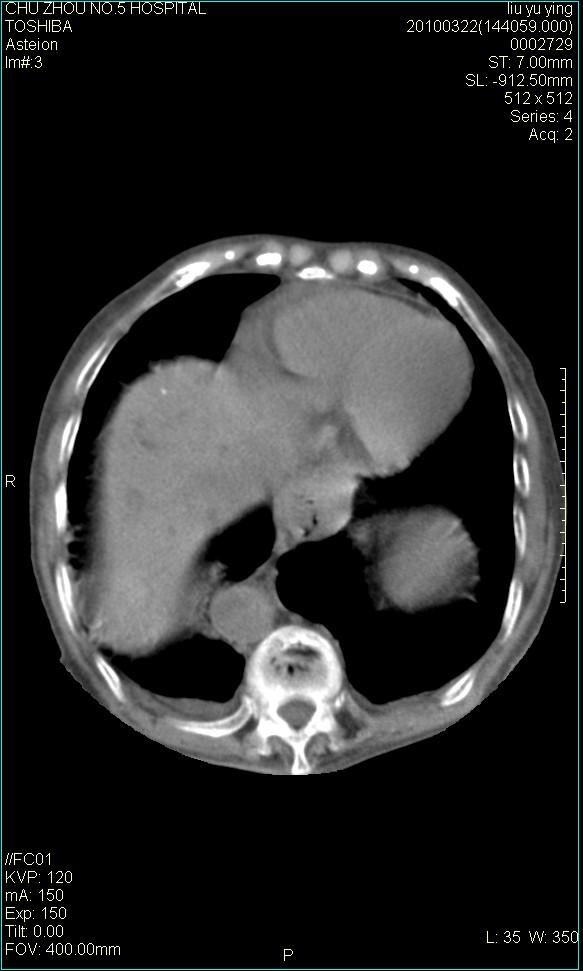

以下是引用科室第一人在2010-3-23 6:50:00的发言:[br]胆总管下段梗阻,多为肿瘤性病变,巨形胆囊,胆囊炎胆囊窝积液。[br]双侧胸腔积液,右降

以下是引用随光逐影在2010-3-23 8:12:00的发言:[br]1)胆系低位梗阻(肝内外胆管扩张,胆囊增大),原因待查。2)胆囊炎。3)双侧少量胸腔积液。4)降主动脉迂曲。